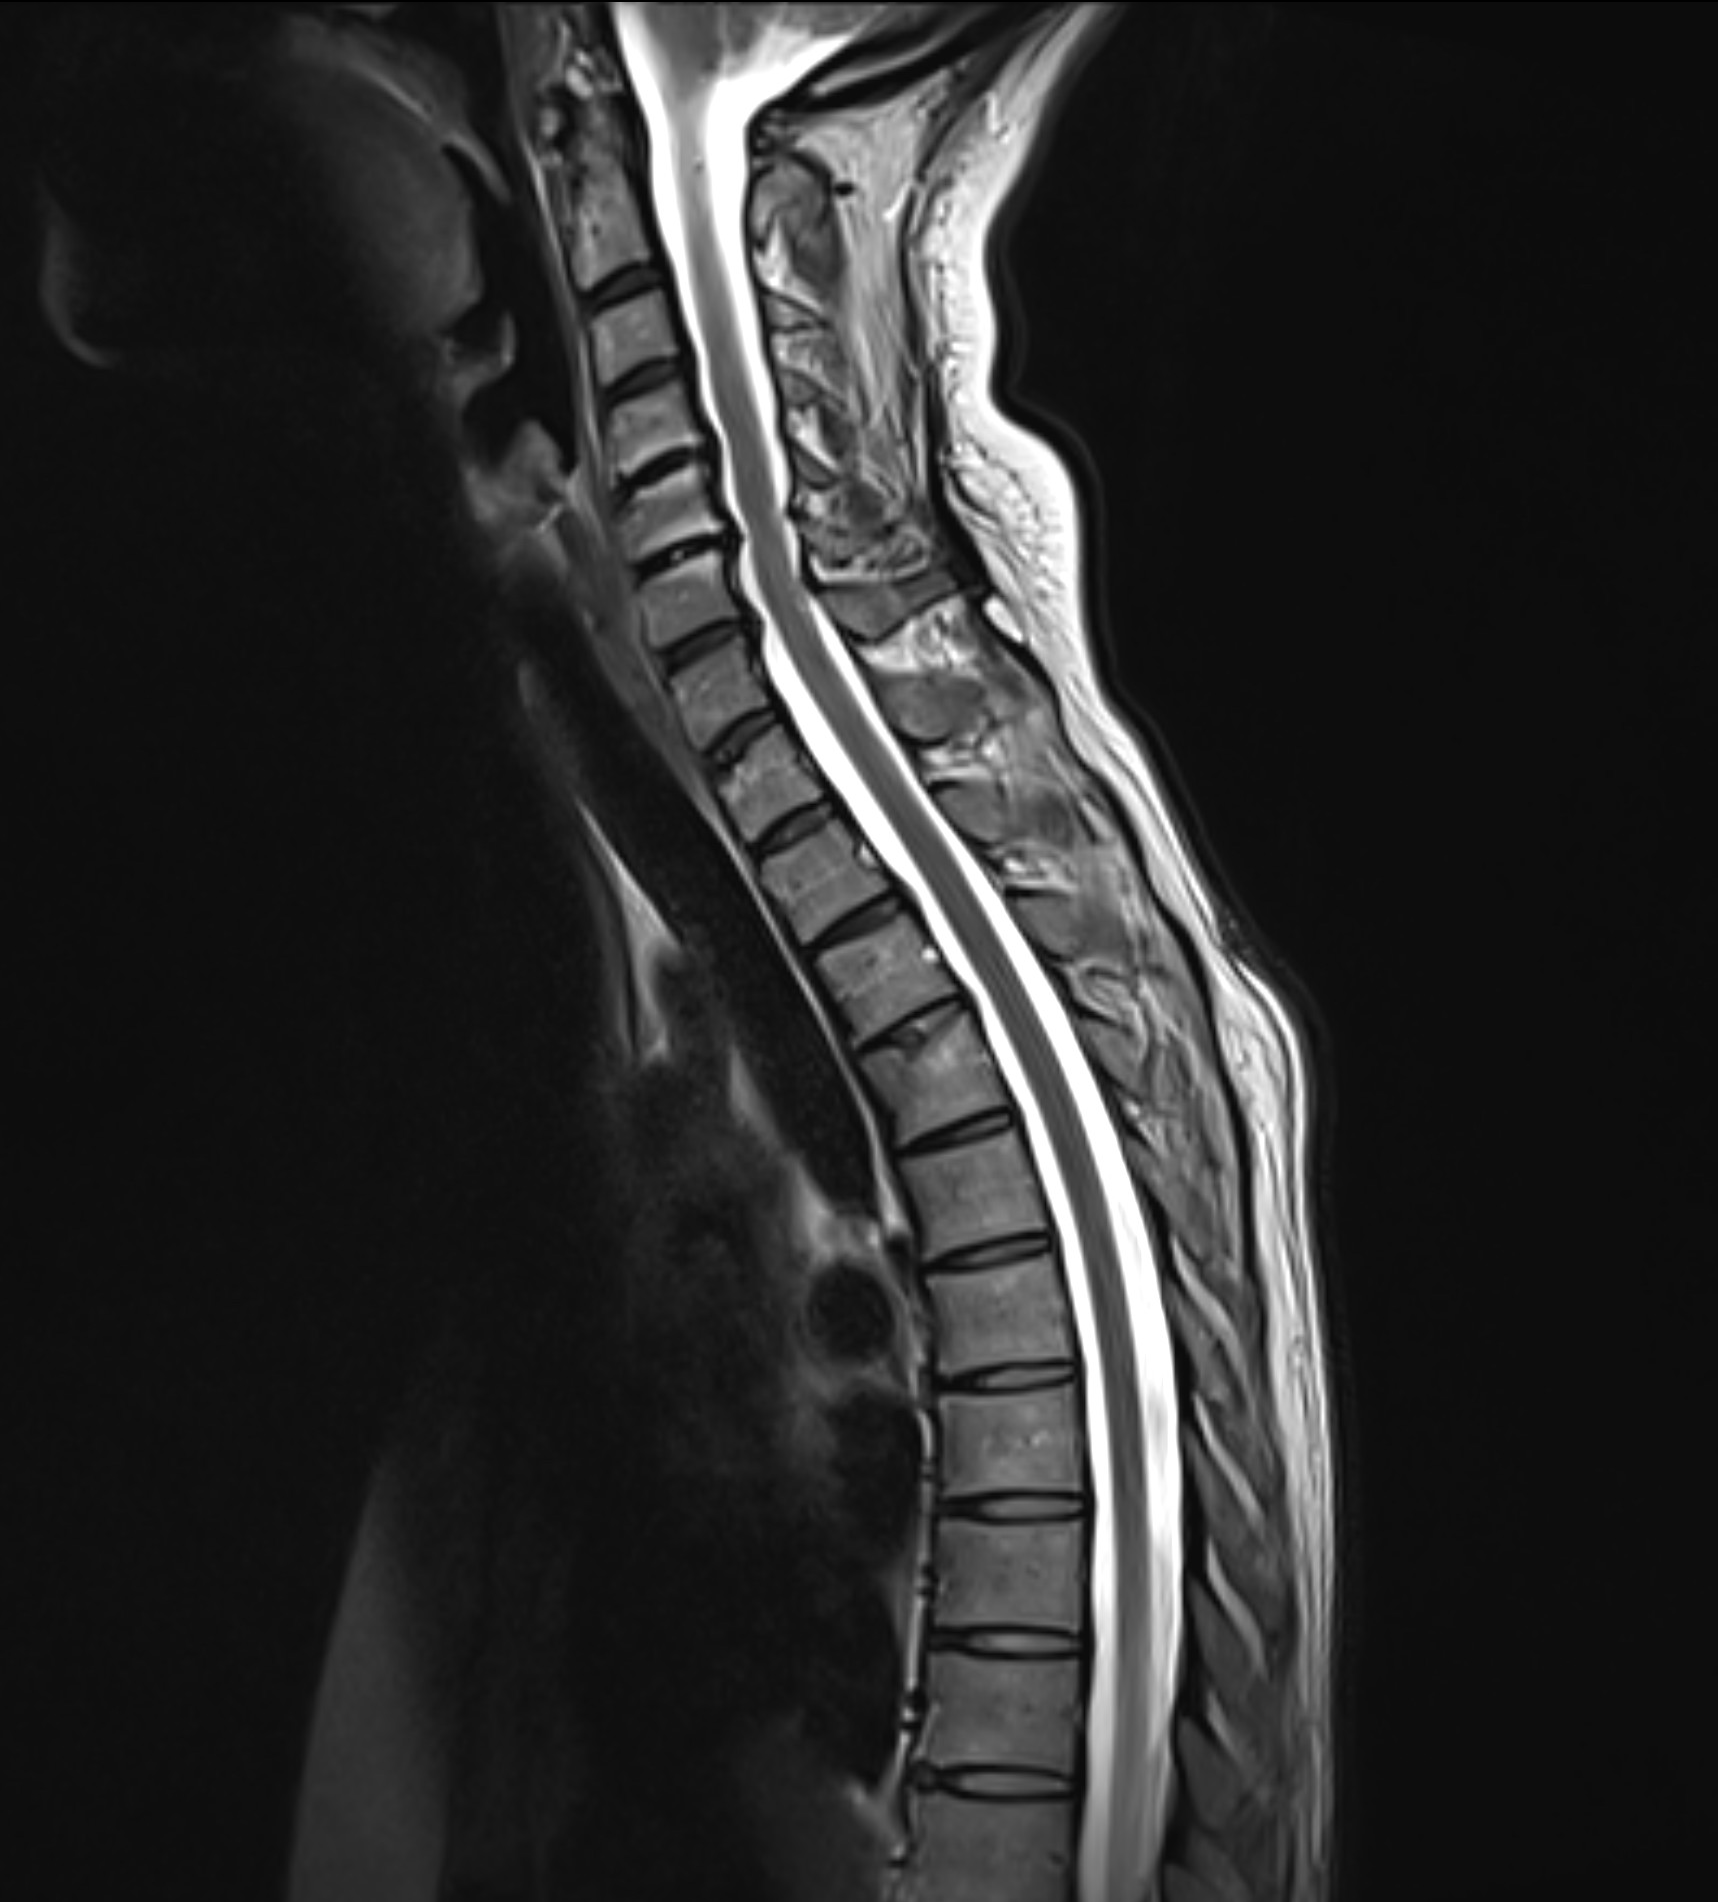

Magnetkameraundersökning (MR) av hela ryggraden – hals-, bröst- och ländrygg

MR Helrygg är en avancerad magnetkameraundersökning som omfattar hela ryggraden, från halsrygg (cervikal) och bröstrygg (thorakal) till ländrygg (lumbal). Undersökningen ger en detaljerad bild av samtliga delar av ryggraden och omgivande strukturer, vilket gör det möjligt att identifiera både akuta och kroniska förändringar. Eftersom undersökningen täcker alla ryggsegment rekommenderas den framför allt för dig som har mer omfattande eller diffusa besvär som inte kan lokaliseras till en specifik del av ryggen.

Undersöknigen omfattar samtliga tre huvudsegment i ryggraden.

MR Halsrygg (cervikal ryggrad)

Undersökning av nackens kotor, diskar och ryggmärg. Här kan bland annat diskbråck, nervpåverkan och förträngningar i spinalkanalen identifieras.

MR Bröstrygg (thorakal ryggrad)

Bröstryggen utgör den mellersta delen av ryggraden och skyddar ryggmärgen genom bröstkorgen. MR kan påvisa exempelvis inflammation, tumörer eller strukturella förändringar.

MR Ländrygg (lumbal ryggrad)

Ländryggen är ett vanligt område för smärta och nervpåverkan. MR används ofta för att upptäcka diskbråck, spinal stenos och degenerativa förändringar.